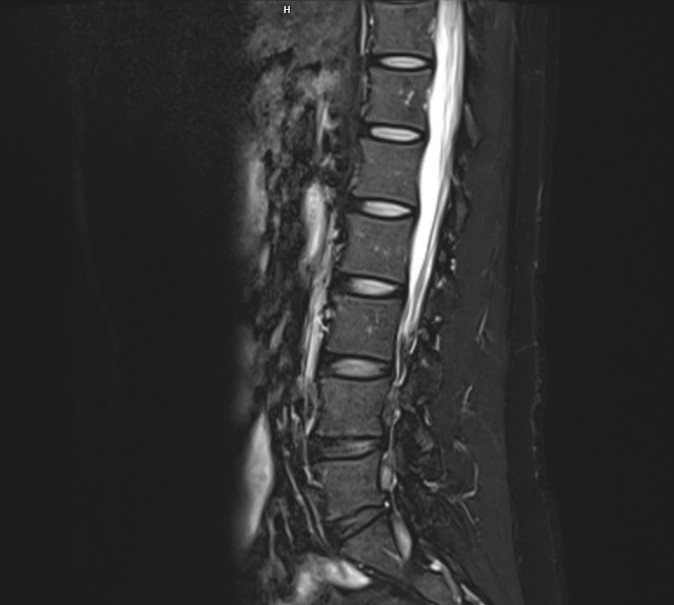

腰椎

椎间盘突出 · 是否需要手术?

- 在临床背景下审阅椎间盘突出影像

- 神经压迫评估

- 手术合理性明确化 — 基于循证医学

- 骨科影像专家分析

脊柱手术复查